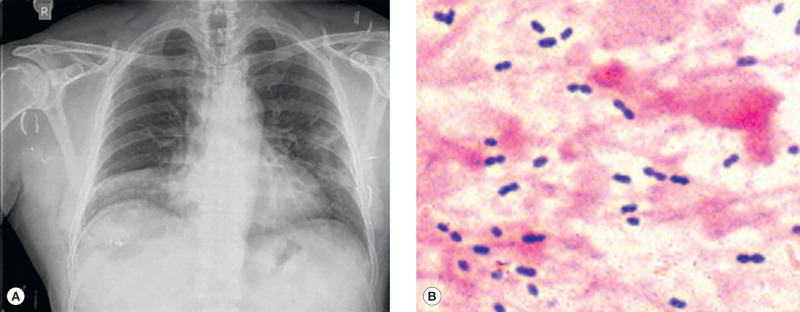

Sputum examination is an important aid in the diagnosis of pneumonia: color, amount, consistency, and odor. Mucopurulent sputum is commonly found in bacterial pneumonia or bronchitis. Scanty, watery sputum is often noted in atypical pneumonia; “rusty” sputum is seen in pneumococcal pneumonia; and currant-jelly or dark-red sputum suggests Klebsiella pneumoniae. Foul-smelling sputum is associated with anaerobic infections due to aspiration, lung abscess, and necrotizing pneumonia. A blood count usually reveals leukocytosis in bacterial pneumonia, a normal white cell count or leukopenia in viral infection, and eosinophilia in parasitic infection. When available, chest x-ray, serum procalcitonin, and C-reactive protein can be obtained (Fig. 1.3 ). Naso-pharyngeal swabs for polymerase chain reaction (PCR) can help establish the diagnosis of specific viral infections if available.

Fig. 1.3.

(A) Pneumococcal pneumonia, right middle lobe. (B) Gram-positive diplococci (sputum).